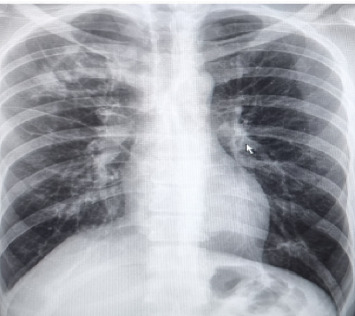

Opportunistic fungal infections (OFIs) are common among human immunodeficiency virus (HIV) -positive patients, especially in those with delayed diagnosis and treatment. Patients with severe HIV/AIDS with clusters of differentiation 4 (CD4) counts less than 100 are significantly prone to develop multiple OFIs. In the current study, we present a case of co-infection of pulmonary aspergillosis and cryptococcal meningitis in a late-diagnosed HIV patient with a low CD4 count.